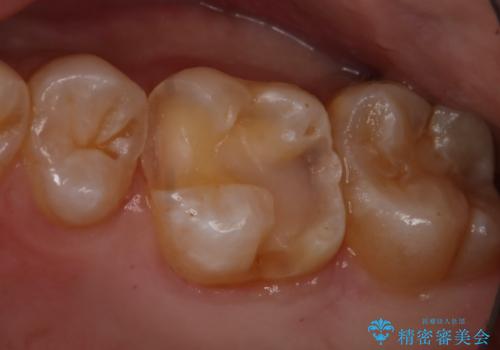

- 左上6番の銀歯のやり変えを希望し来院された患者様です。

切削量・形態を考慮し、セラミックインレーでの治療を計画しました。